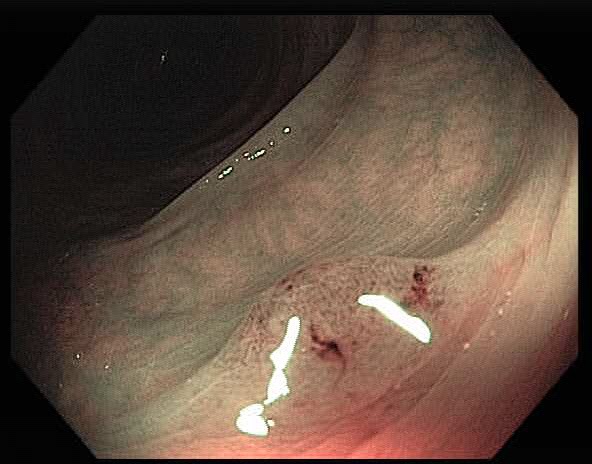

Colonoscopy is the main diagnostic procedure to detect and recognize polyps located on colorectal walls. The accurate detection and correct classification depend on the skills and experience of the endoscopists, however, even for experienced endoscopists, working on conventional colonoscopy for long hours leads to mental and physical fatigue and degraded analysis and diagnosis. Other factors that may affect the classification results include varying illumination conditions, variant texture and appearance, and occlusion. Moreover, different types of polyps are hard to differentiate since they may exhibit a very similar appearance with a subtle difference, as shown in Fig 1. It requires a thorough examination of fine details to distinguish one category form the other. Therefore, an accurate and effective automatic computer-aided system for colonoscopy is required to help endoscopists to detect and classify the type of polyps. This automated recognition mechanism can also be used as a second opinion to determine whether a further biopsy is required for diagnosis, which in turn will greatly reduce the cost of diagnosis. In addition, such an intelligent system can also be used as an educational resource for gastroenterology trainees to reduce the learning curve and cost.

![]() |